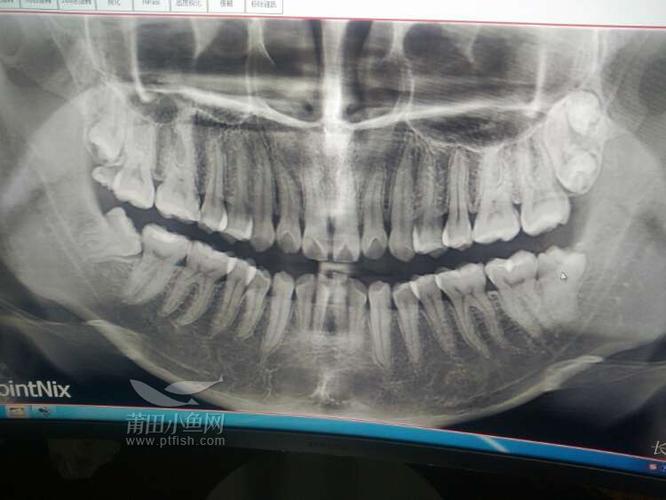

正常侧脸牙齿x光,正常人侧脸与龅牙侧脸

正常牙齿x光

标准牙齿侧面x光片